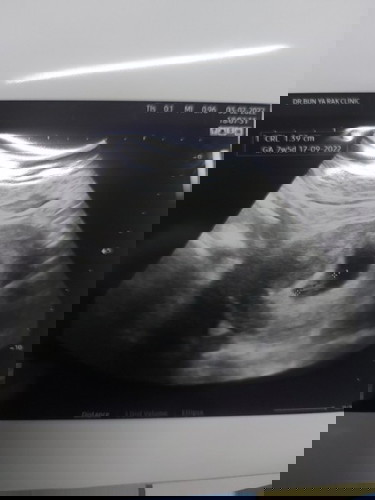

ซาวช่วง8วีคค่ะ เห็นตัวน้องกับหัวใจที่เต้นอยู่ด้วยค่ะ ตอนนี้12วีคแล้วค่ะ เดี๋ยวสัก12วีคขึ้นไปเราจะเห็นตัวน้องชัดขึ้นนะคะ #ท้องคนที่2

8+6วีค ภาพไม่ค่อยชัด ซาวด์ รพ.รัฐค่ะ ตอนนี้32+6วีค

รูปช่วง 8w6d ค่า ปัจจุบัน20w1d แย้วว💕